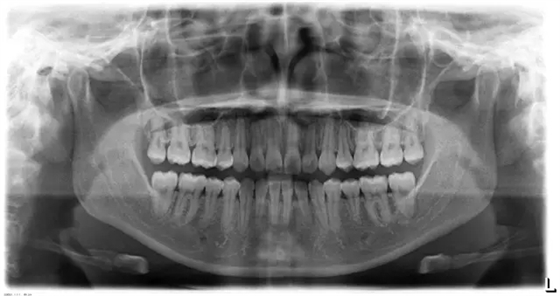

患者側(cè)面凸,鼻唇角較銳,笑時(shí)露齦笑明顯上下牙列擁擠,磨牙尖牙Ⅱ 類關(guān)系,3 度的深覆牙合,上頜中切牙伸長內(nèi)傾拔除上頜雙側(cè)的第一前磨牙,先粘上頜高轉(zhuǎn)矩的自鎖托槽排齊牙列,唇向開展上頜切牙,有一定的覆蓋,粘下頜標(biāo)準(zhǔn)轉(zhuǎn)矩托槽,上頜 1, 2 之間植入種植支抗壓入,同時(shí)后牙 5, 6 之間植入種植支抗內(nèi)收前牙,打開咬合關(guān)閉間隙。治療關(guān)鍵:前牙轉(zhuǎn)矩的控制第 1 個(gè)月 上頜粘上 Damon Q 高轉(zhuǎn)矩托槽,上 .014 熱激活 NiTi 絲。第 3 個(gè)月 上換 .014 x .025 熱激活 NiTi 絲。第 5 個(gè)月 上頜基本排齊,覆蓋增大,上換 .017 x .025 NiTi絲,下頜粘托槽,下 .014 熱激活 NiTi 絲。第 7 個(gè)月 上 .017 x .025 NiTi 絲加搖椅,下?lián)Q .014 x .025 熱激活 NiTi 絲第 9 個(gè)月 上頜換 .019 x .025 NiTi 絲加搖椅,下頜換 .017 x .025 NiTi 絲第 11 個(gè)月 下頜換 .019 x .025 加搖椅,上頜 1, 2 之間, 5, 6 之間植入種植釘,下頜出現(xiàn)散隙。第 13 個(gè)月 上頜換 .019 x .025ss 加搖椅,前牙種植釘用 Power Chain 壓低前牙(每側(cè) 100g),后牙種植釘關(guān)閉間隙(每側(cè) 150g),下?lián)Q .019 x .025ss,Power Chain 關(guān)閉間隙。第 19 個(gè)月 上頜前牙基本壓低到位去除前牙種植釘,繼續(xù)用關(guān)閉間隙,下頜散隙關(guān)閉。

第 22 個(gè)月 上頜覆蓋變小,去除 5, 6 之間種植釘,后牙前移關(guān)閉間隙。第 30 個(gè)月 患者未配合中線牽引,下中線仍有 1mm 右偏,患者對矯治效果滿意要求拆除,拆除固定矯治器,取模制作壓模保持器。 1.骨性 Ⅱ 類的患者內(nèi)收前牙時(shí)需對上頜前牙的轉(zhuǎn)矩進(jìn)行較好的控制才能獲得良好的面型和唇部形態(tài)。 2.露齦笑的患者治療前要分析其病因是唇、牙齦、牙齒、牙槽骨、上頜骨或多種因素結(jié)合,再制定矯治方案。 3.Ⅱ 類第二分類伴露齦笑的患者的上頜前牙移動軌跡是唇向開展-壓低-整體內(nèi)收。 4.Ⅱ 類第二分類牙齒舌傾比較厲害的情況,上頜中切牙慎用樹脂咬合墊。 5.壓低前牙或控根移動時(shí)容易發(fā)生牙根的吸收,需輕力緩慢的移動。